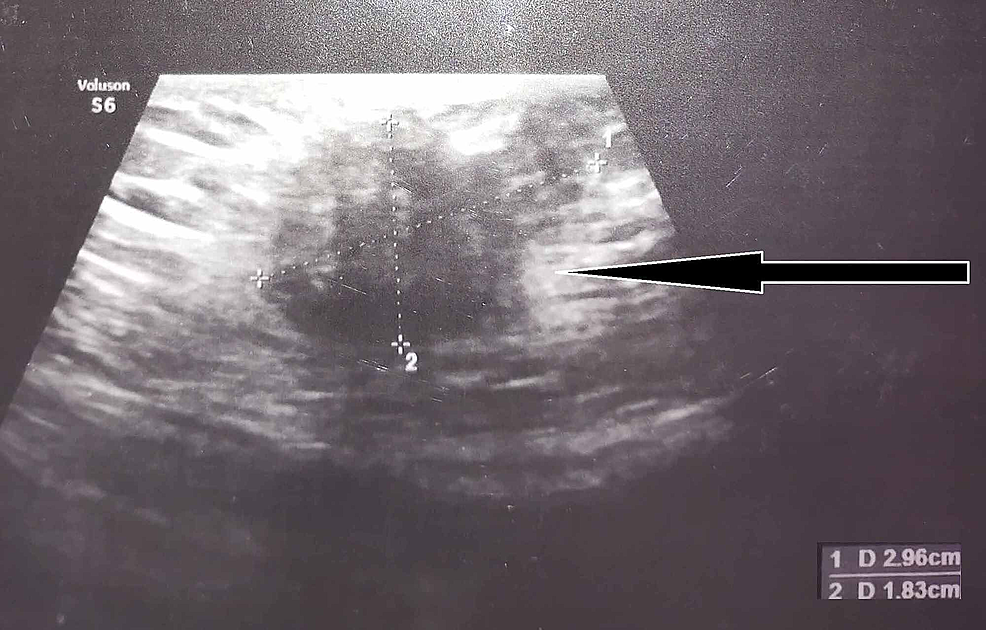

From www.wjgnet.com

Reliable clinical and sonographic findings in the diagnosis of Scar Endometriosis C Section The pfannenstiel incision of a cesarean section scar is the most common site of abdominal wall endometriosis with an incidence. Cesarean scar endometriosis (cse) is the most common type of abdominal wall endometriosis (awe). We report our experience in managing cesarean scar endometriosis (cse) and emphasize the diagnosis and treatment options. The most common symptom of endometriosis and adenomyosis after. Scar Endometriosis C Section.